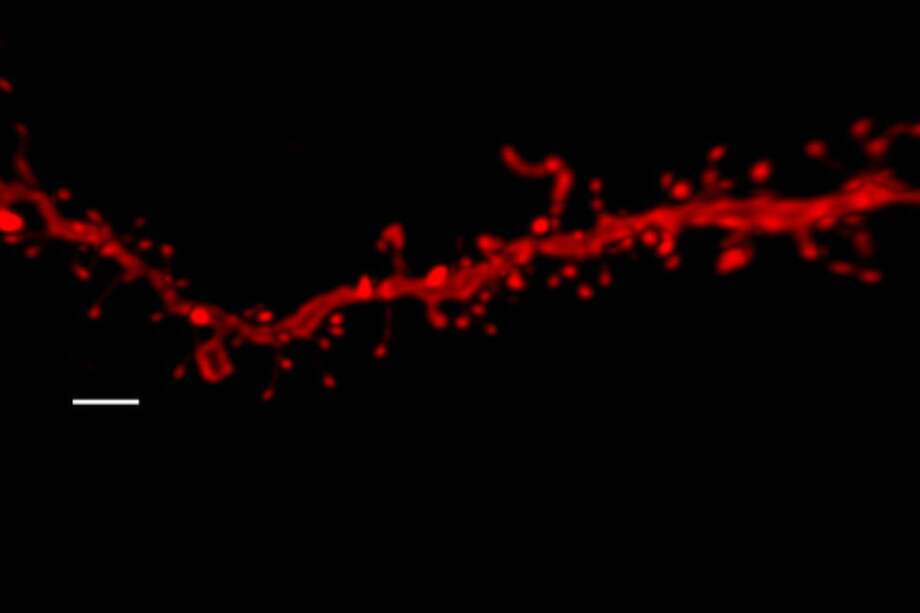

“Los ratones adolescentes tratados con THC y expuestos al estrés exhiben un deterioro en la extinción del miedo en la edad adulta. Sin embargo, este efecto no se observó en los animales expuestos a estos dos mismos factores por separado”, detalla Berrendero. Además, la resistencia a la extinción del miedo se asoció con una disminución de la actividad neuronal en la amígdala basolateral y la corteza prefrontal infralímbica, lo que sugiere una desregulación a largo plazo del circuito que regula el miedo.